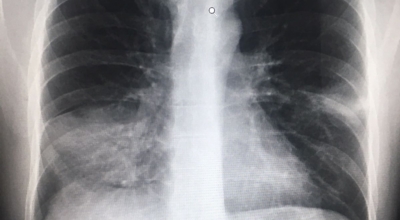

4. 폐렴 진단: 어떻게 폐렴을 확인할 수 있을까요?

폐렴은 증상만으로는 정확하게 진단하기 어려우므로, 다음과 같은 검사를 통해 진단합니다.

- 흉부 X선 촬영: 폐의 염증 부위를 확인하는 가장 기본적인 검사입니다.

- CT 촬영: X선 촬영보다 더 자세한 영상을 얻을 수 있어 폐렴의 위치와 범위를 정확하게 파악할 수 있습니다.